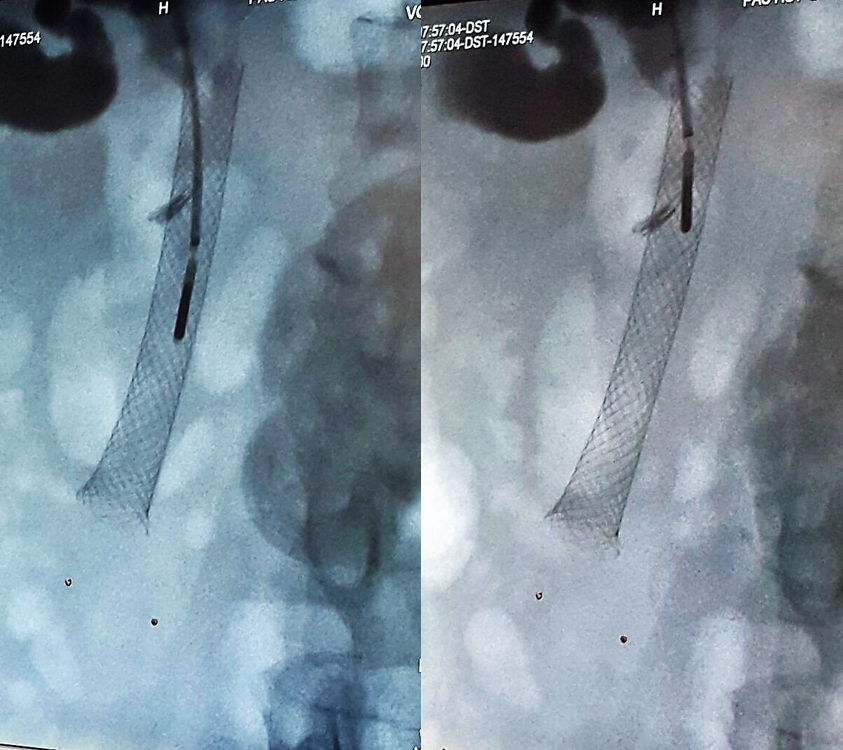

The doctors applied microwave energy to destroy tumor growth prior or post bile-duct stent installation to reestablish and maintain normal bile flow. The microwave energy is applied to the tumors in and around the duct and stent with percutaneous transhepatic cholangiography (PTC) using fluoroscope (real-time x-ray) images of liver, bile-ducts and gallbladder-ducts. A long flexible needle-catheter is inserted into the liver under fluoroscopy to locate and identify blockages using contrast dye. Once the blockage is identified, a smaller diameter catheter with microwave antenna is introduced into first catheter, the antenna is positioned along the duct and the microwave energy is applied using preset temperature and time durations. The antenna is retracted along the duct and the energy application is repeated until the desired length of the duct is treated. The doctors would remove the microwave catheter and verify bile-duct flow with fluoroscopy. The microwave energy application is controlled with direct temperature feedback from the ablation antenna during the procedure to ensure safety and efficacy.

AveCure® microwave ablation system is successfully treating tumors in bile-duct using a minimally invasive technique - the percutaneous transhepatic cholangiography (PTC) incision through the skin to access the tumor through the liver and the patient is left with a small hole in the skin, which quickly heals with almost no scar after the procedure. AveCure® system utilizes a smart antenna in either probe or catheter format and microwave energy controller to select the correct size, temperature and timer settings appropriate for safe, effective and predictable treatment.